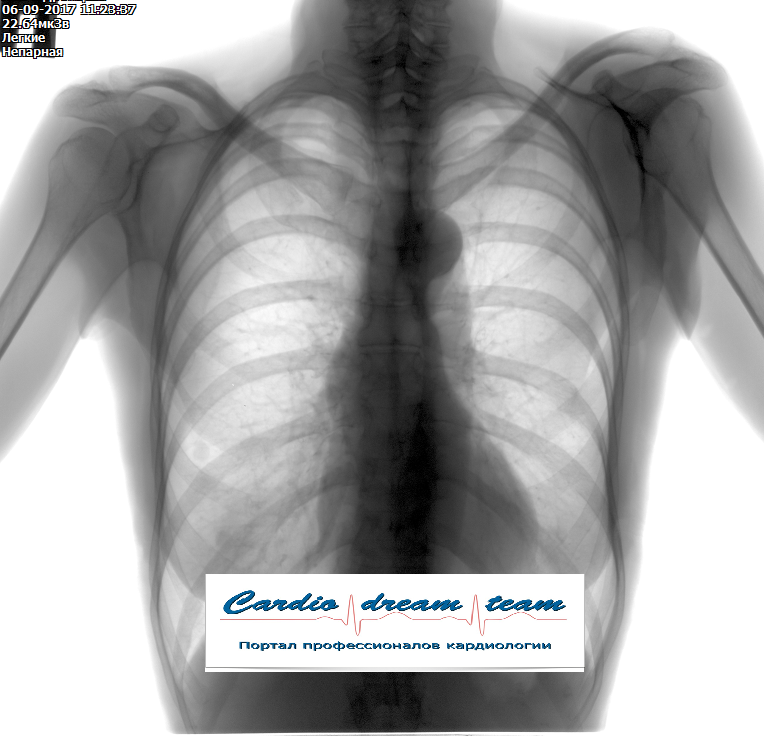

Сосудистая мальформация